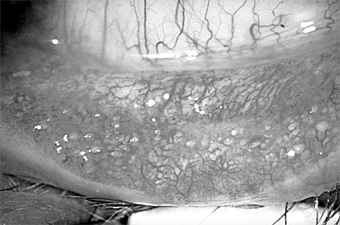

Treatment of ocular rosacea consists of the elimination of hot, spicy foods and of alcoholic beverages that cause dilation of the facial vessels. Any secondary staphylococcal infection should be treated (Figure 5-18). A course of oral tetracycline or doxycycline is often helpful, and a smaller maintenance dose may be needed to control the disease.

Figure 5-18

Figure 5-18: Multiple concretions on the inferior tarsus. These are often associated with chronic lid disease caused by staphylococcal species.